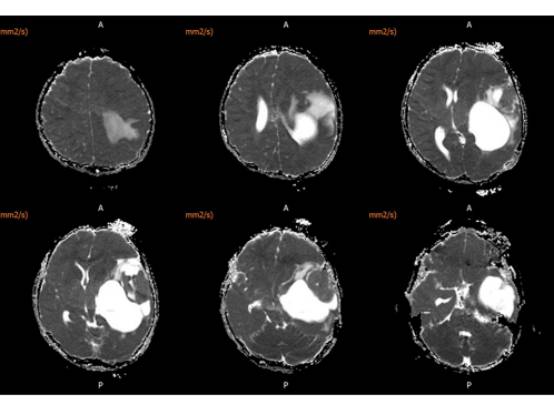

MR平扫及增强示:

MR

左侧颞叶见大块状等长T1等长T2异常信号,FLAIR呈高新,DWI(b=1000)实质部分呈稍高信号,ADC实质部分呈等信号,边界尚清,周围脑实质受压。注入GD-DTPA后病变实质部分呈明显强化。